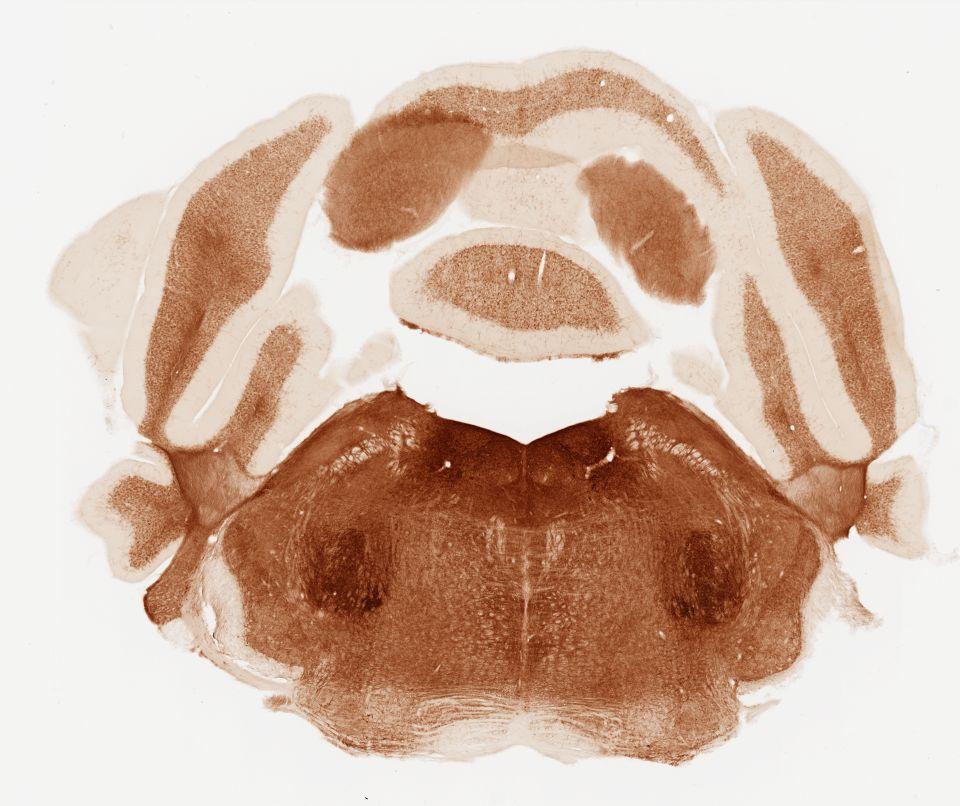

Datasets -> Mus Musculus -> AChE, (Acetyl Cholinesterase), coronal, histo, Whole-Brain, adult

[ Metadata ]   ·   Source: Shawn Mikula

Displaying Sections 41 thru 80 of 88 Sections for this Dataset